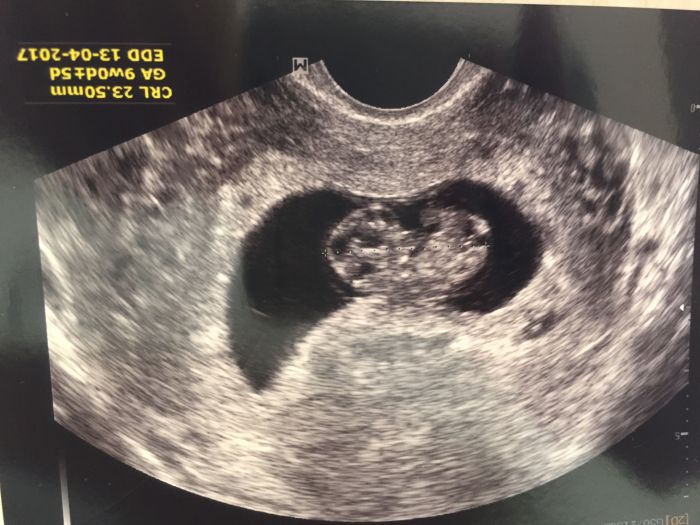

Tak tehulky dnes jsem byla u dr a nejsem 6+3 ale 7+1

Takže zafolka tam je i srdíčko boucha o zavot . :-)

Ahoj holky, gratuluji k úspěšným kontrolám a Peti neboj, příště už bude prcek určitě větší ;) my máme za sebou dneska taky kontrolu. 9+0 mimco hezky roste, dostala sem průkazku a další kontrola za 4 týdny stejně tak i screening. Pf to je doba :-D tak hezky den preju :)